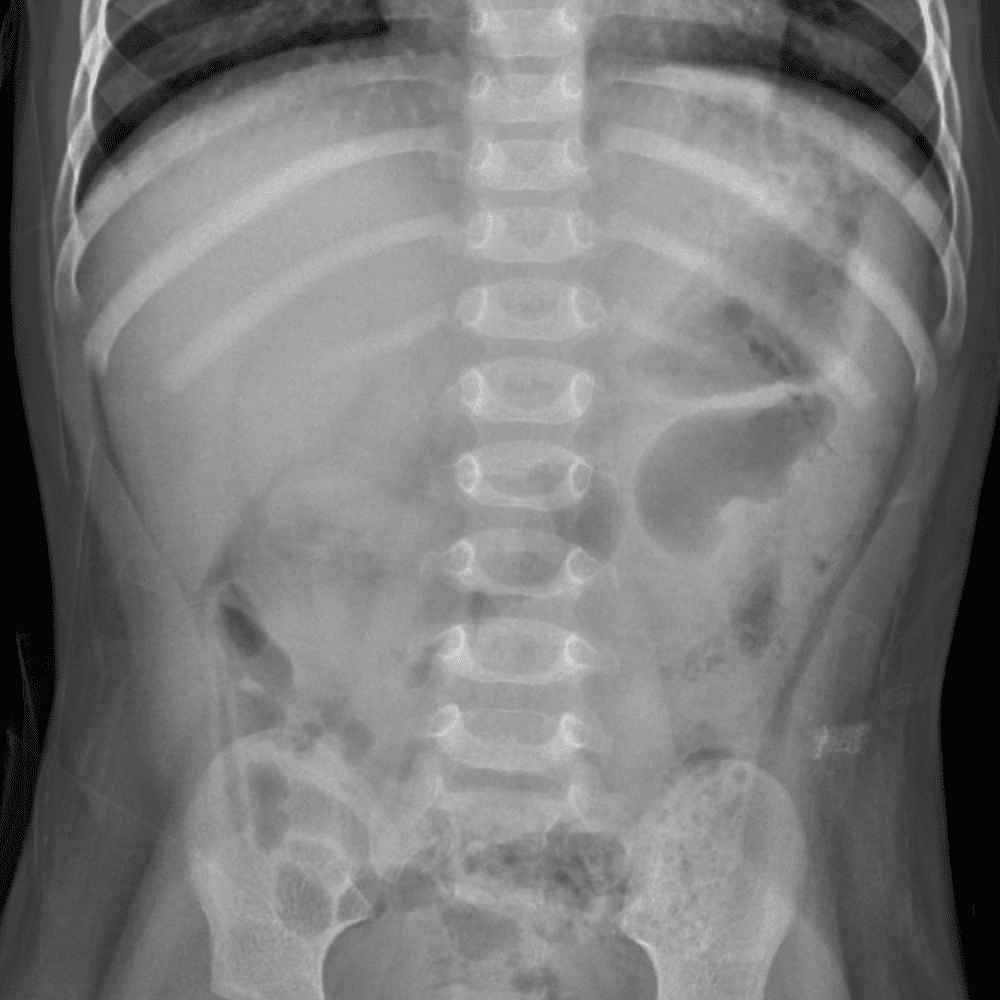

Peds Abdomen

Practice

Simulates call by including subtle or difficult cases and some normals.

30 cases